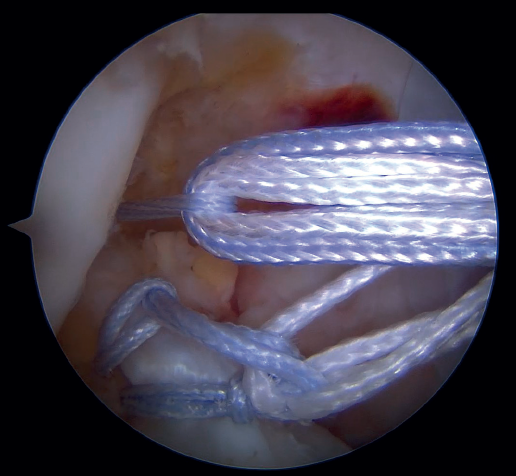

Outside the knee, the threads are loaded into a knotless anchor implant with a tape that will act as anterior reinforcement of the ACL when attached to the tibia. Once the implant has been loaded, it is inserted into the previously prepared site. This step is facilitated when viewing is made from the anteromedial portal, as it affords a better perspective of the zone (Figure 5). Once the implant has been inserted, the suture threads are cut at the level of the condylar wall.

With vision through the anterolateral portal, the tibial guide of the ACL is placed in the central zone of its distal insertion, and a tunnel is made with a 2.4 mm cannulated drill through which a loop-ended nitinol is passed and retrieved through the accessory anteromedial portal. The nitinol serves as a retriever, to load the tape through it and pass it through the tibial tunnel. Once the tape is retrieved, it is secured to the tibial cortex with a knotless anchor implant or button, tightening the tape with the knee in near full extension. If a threaded implant is used, it is important to check that no implant threads protrude at the cortex, as this could cause discomfort in the future.